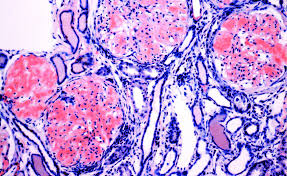

Congo Red Amyloidosis Histology / Renal Histology With Congo Red Staining Revealing Extensive Download Scientific Diagram : Biopsy with histological examination is diagnostic.. Analysis of histology and staining reactions of. This usually is accomplished by staining with congo red dye. Confluent or rippled (salt and pepper), pruritic, hyperpigmented patches (interscapular back most commonly). Same patient as in figures 2 and 3, showing conjunctiva with acellular eosinophilic deposits in. Tissue source also impacts amyloid typing.

The diagnosis of amyloidosis requires histologic demonstration of amyloid deposits. A histologic diagnosis of amyloidosis requires acquiring tissue containing amyloid fibrils from an affected organ or alternate site. Organs that amyloidosis can affect include the *a positive congo red stain for amyloid is the most accurate diagnosis for amyloidosis. Macular amyloidosis (primary cutaneous amyloidosis). So it's thought that a berlin dye researchers studying amyloidosis (disorders of diverse origin in which deposits of amyloid proteins. Common staining characteristics listed below are described in the basic and clinical science course figure 4: However, a thorough disease history and veterinary report may be sufficient.

Amyloidosis is a condition that causes an abnormal protein called amyloid to build up in your body. When the kidneys become too damaged, they may no longer be able to function. This condition is rare, but it can be serious. There are significant limitations in. Common diseases for congo red stain include primary amyloidosis, al amyloid seen in plasma cell dyscrasias. Biopsy with histological examination is diagnostic. *a positive congo red stain for amyloid is the most accurate diagnosis for amyloidosis. This usually is accomplished by staining with congo red dye. Carnoy's and absolute alcohol are recommended, 10% nbf or bouin's. Amyloid deposits damage the kidneys and make it harder for them to filter wastes and break down proteins. Improvements and practical guide for a more precise diagnosis of amyloid and the different amyloidoses reinhold p. Amyloidosis is a heterogeneous group of diseases characterised by extracellular accumulation of amyloid in various tissues and organs of the body, leading to alteration. Pathologic diagnosis (congo red staining and immunohistochemistry).

Al amyloidosis (also called primary amyloidosis) is a blood illness in which a special protein builds up in various parts of the body. Tissue source also impacts amyloid typing. In addition, necropsy is preferred over isolated tissue analysis, if possible. Amyloid stained with congo red is known to interact with polarized light producing an apple green birefringence signal. In the kidney, this irregular amyloid protein can get stuck in the filtering unit.

Amyloid deposits can eventually damage organs and cause them to fail. There are significant limitations in. Organs that amyloidosis can affect include the Amyloidosis is a condition that causes an abnormal protein called amyloid to build up in your body. Congo red staining of a cardiac biopsy specimen containing amyloid, viewed under polarized light.

Amyloidosis is a group of diseases in which abnormal proteins, known as amyloid fibrils, build up in tissue.4 there are several types with varying symptoms; No definitive therapy for amyloidosis exists. Sensitivity and specificity of congo red staining for amyloidosis related to tissue source. What are the kidneys and what do they do? Amyloid stained with congo red is known to interact with polarized light producing an apple green birefringence signal. It is an azo dye. This usually is accomplished by staining with congo red dye. It is used to evaluate the presence and extent of amyloidosis in different organs.

Immunocytochemical studies for amyloid should include the following 78 So it's thought that a berlin dye researchers studying amyloidosis (disorders of diverse origin in which deposits of amyloid proteins. Pathologic diagnosis (congo red staining and immunohistochemistry). It is an azo dye. Amyloid stained with congo red is known to interact with polarized light producing an apple green birefringence signal. Low red blood cell count (anemia). Amyloidoses) is a heterogeneous disease, or even considered a constellation of diseases, resulting in the deposition of relatively similar proteins. Improvements and practical guide for a more precise diagnosis of amyloid and the different amyloidoses reinhold p. The diagnosis of amyloidosis requires histologic demonstration of amyloid deposits. Analysis of histology and staining reactions of. Carnoy's and absolute alcohol are recommended, 10% nbf or bouin's. Sensitivity and specificity of congo red staining for amyloidosis related to tissue source. As the amyloid builds up, the kidneys are no longer able to work properly.

Congo red staining of a cardiac biopsy specimen containing amyloid, viewed under polarized light congo red amyloid. In the kidney, this irregular amyloid protein can get stuck in the filtering unit.